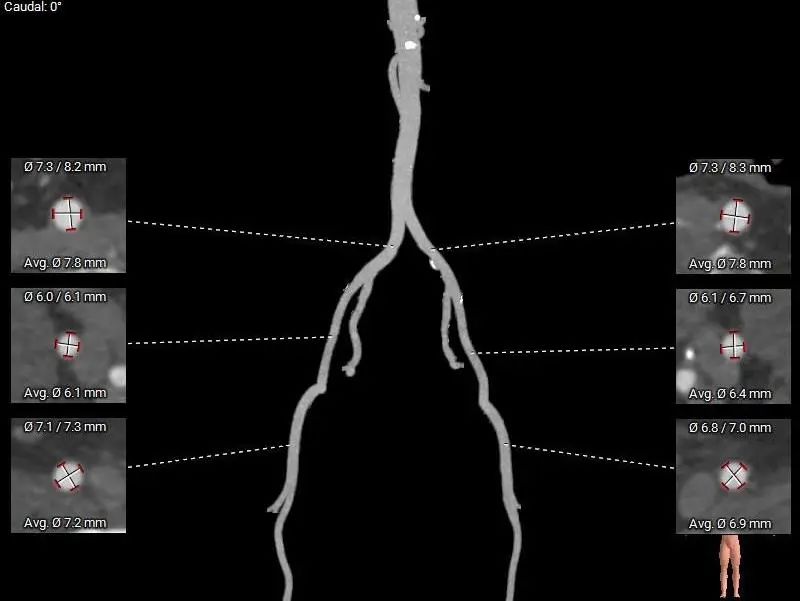

外周入路:

病理特点及手术难点

三叶式主动脉瓣,瓣叶轻中度钙化并明显增厚,人工瓣膜锚定力尚可,左室流出道呈敞口型,综合多平面分析,预估瓣膜释放后有向下位移风险及瓣周漏可能。

左右冠开口高度稍低,综合瓦氏窦及窦管交界内径综合判断,预估左右侧冠脉阻挡风险适中,术中可根据球扩结果进一步判断,必要时行冠脉保护。

左室心腔内径尚可,结合超声及患者情况,术中密切观察血流动力学变化,可预装瓣膜并备体外循环。

非横位心,主动脉弓角度及弓距可,预估术中输送器过弓、跨瓣顺利。

右侧股动脉为主入路,左侧股动脉为辅入路。

直径20mm TaurusAtlas球囊进行预扩,同时预装TaurusElite AV23瓣膜。瓣环下0-2mm开始定位释放。释放过程中多角度造影,超声辅助定位确定瓣膜最终位置。释放后再次造影确定佐证。